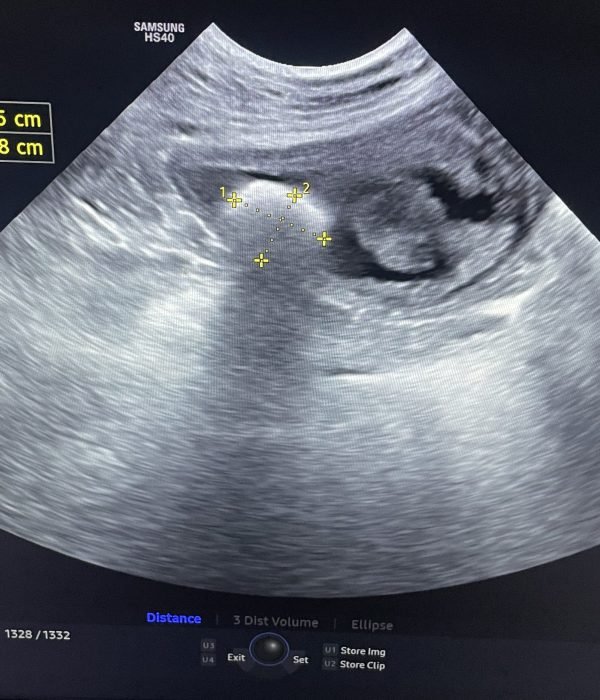

Our hospital is equipped with advanced digital dental and whole-body radiography, as well as ultrasound, to support accurate diagnosis and treatment of a wide range of conditions, including pulmonary, cardiac, gastrointestinal, and urogenital diseases.

Images are immediately available for review by your veterinarian, and for cases that require additional expertise, both radiographs and ultrasound images can be securely sent for interpretation by a board-certified radiologist and AI-powered screening.

Having these advanced imaging tools on-site allows our veterinarians to make faster, more precise diagnoses and develop targeted treatment plans tailored to your pet’s specific needs.